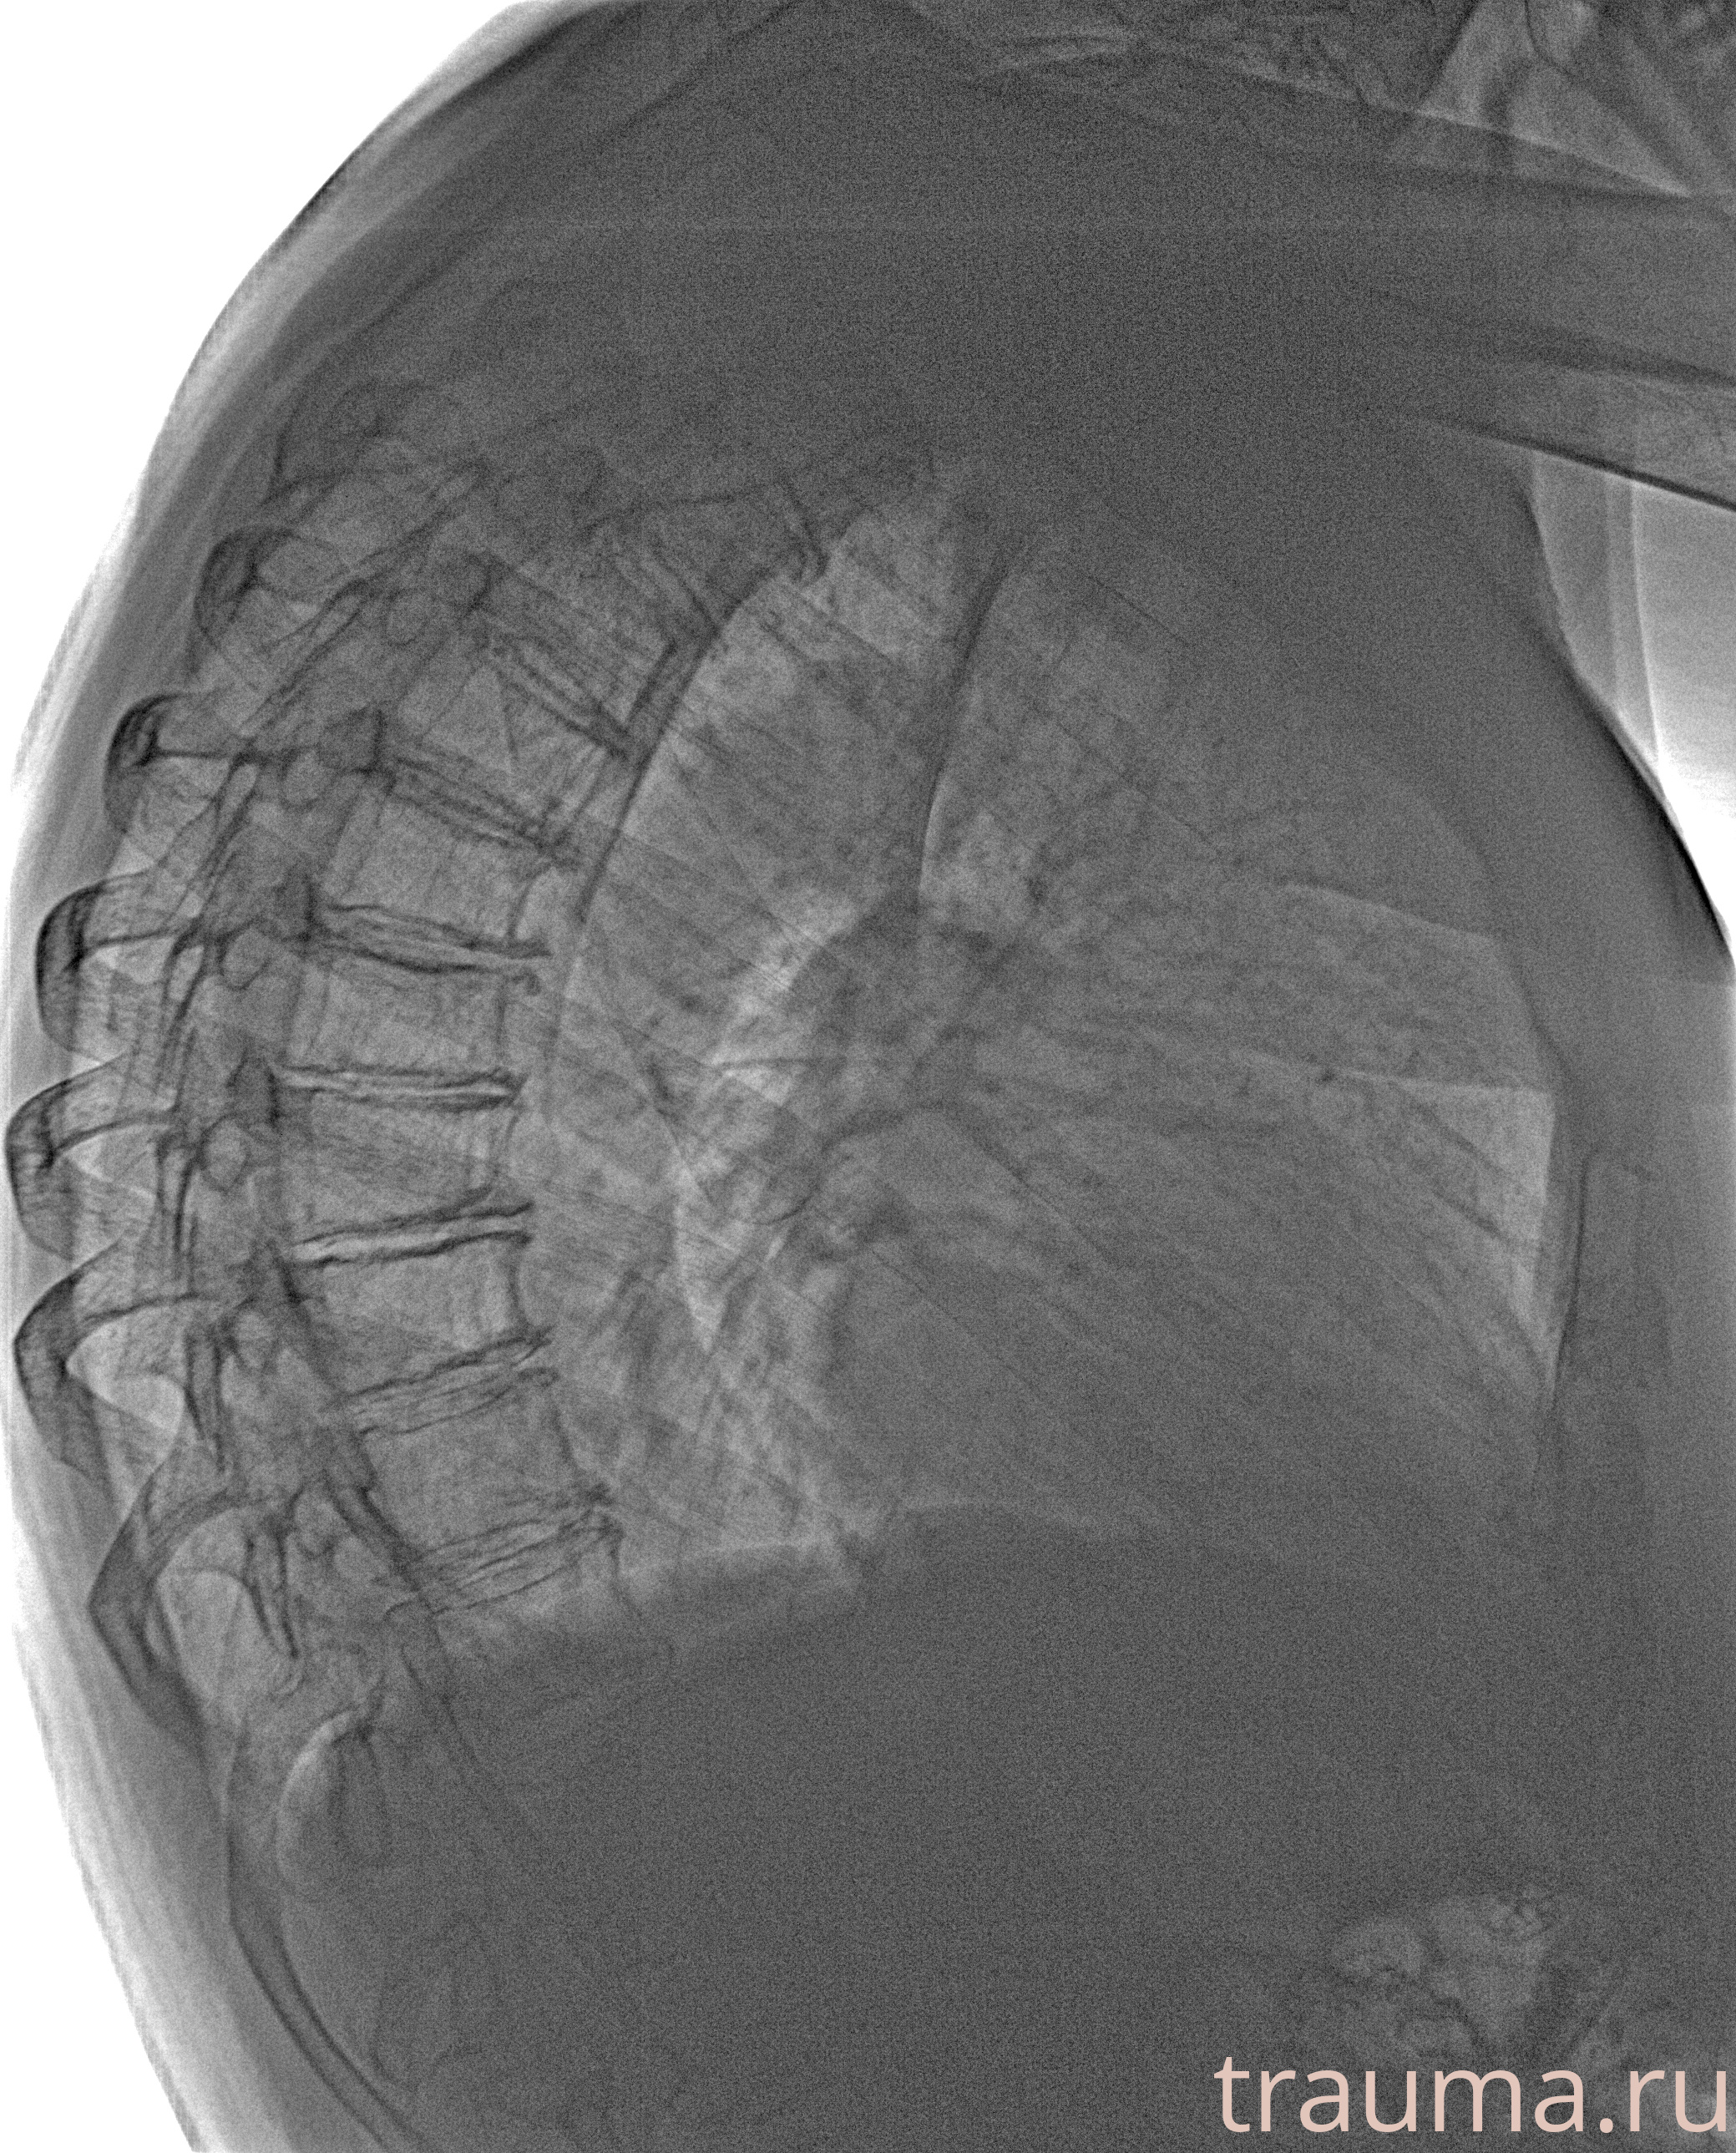

Рентгенограммы

Рентген на дому: по вашему адресу приезжает врач-рентгенолог, травматолог-ортопед с мобильным рентгеновским аппаратом, проводит диагностику травмы или заболевания, делает необходимые рентгенограммы, дает рекомендации по дальнейшему лечению. Получить качественные снимки в домашних условиях возможно благодаря уникальной методике, разработанной МосРентген Центром для института  Склифосовского

при переломе шейки бедра и пневмонии от компании МосРентген Центр - партнера Института имени Склифосовского